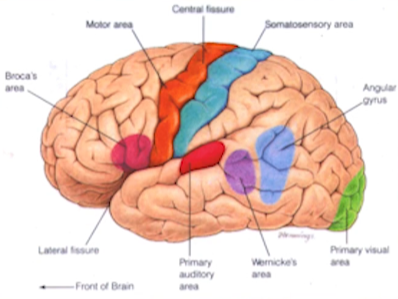

- 大脑结构图二

图1-2 - 品红色:语言中心,损坏则失语

- 橙色:运动皮质区

- 蓝色:整体感觉区

- 红色:听觉皮质

- 紫色:语言中心,损坏则语无伦次

- 绿色:枕叶